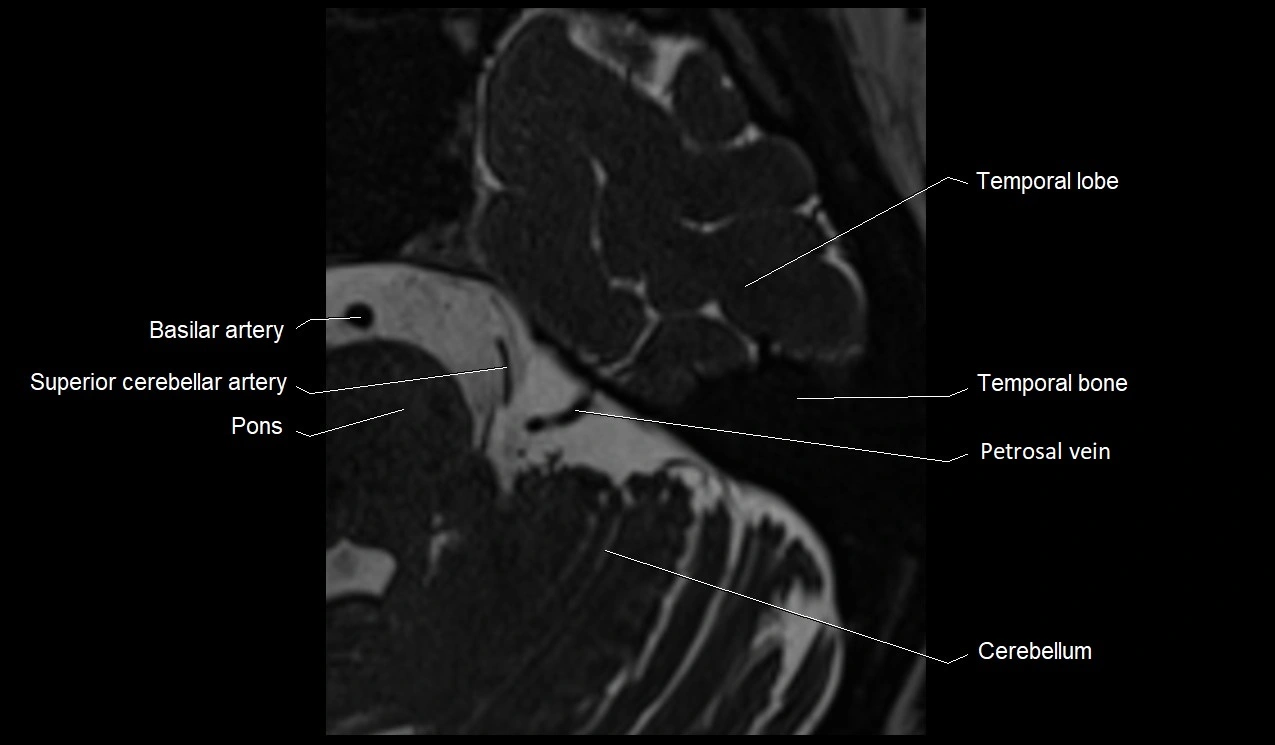

MRI Appearance

• The abducens nerve is a small, thin, linear structure

• Best visualized on high-resolution T2-weighted 3D MRI sequences (e.g., FIESTA or CISS)

• Seen as a hypointense (dark) line running from the brainstem at the pontomedullary junction, traversing the prepontine cistern, and entering Dorello’s canal under the petrosphenoidal ligament, then into the cavernous sinus, and finally the orbit

• May be challenging to visualize in standard MRI due to its small size

• Pathology may be inferred by absence, displacement, or enhancement of the nerve